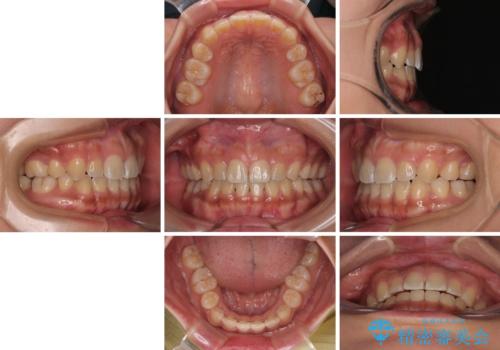

デコボコと捻れて前に飛び出した歯列 抜歯矯正でスッキリした口元に

- 前歯のデコボコと口元の突出感を気にして来院された患者様です。

非抜歯矯正ではデコボコを解消することでより口元が突出してしまうため、上下左右の小臼歯4本の抜歯を行い、ワイヤー装置による矯正治療を行うこととしました。

上顎小臼歯の歯根が左右ともに大きく曲がっており、スペースクローズに時間がかかってしまいました。